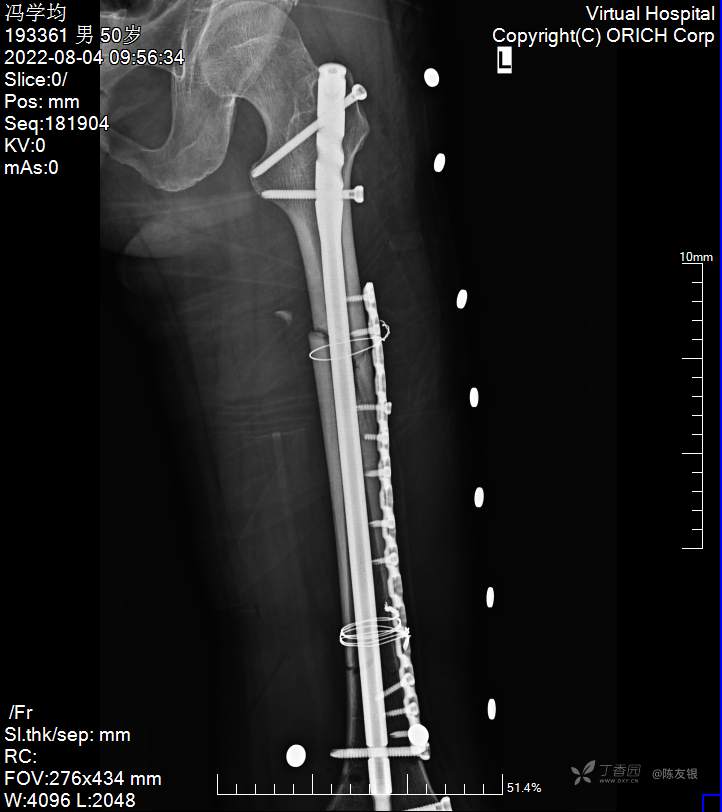

治疗经过:入院后积极完善相关检查,立即急诊在全身麻醉下行剖腹探查术+脾脏切除术+回肠部分切除术+左侧胸腔闭式引流术+左胫骨结节牵引术+多部位清创缝合术,术后给其抗休克、预防感染、输血、纠正血容量、对症治疗,待病情稳定后,2022年8月1日在全麻下行左股骨干多段粉碎性骨折切开复位髓内针、钢板内固定,左锁骨骨折切开复位内固定术,2022年8月8日在全麻行左肩胛骨骨折切开复位内固定术。术后给其预防感染、消肿止痛、活血化瘀、改善微循环、促进骨质生长、对症治疗,逐渐加强功能锻炼。术后患者切口一期愈合,逐渐康复出院。

(1)股骨干骨折闭合复位失败,行切开复位后,内固定物方式:只用髓内针?只用钢板?钢板髓内针同时使用

股骨干多节段骨折治疗方式是闭合复位髓内针内固定是其金标准。手术前用带刻度的透X线标尺测量健肢大腿全长备案。麻醉成功生效后,患者上牵引床上,手法牵引闭合复位C臂透视发现骨折复位不成功,然后用张英泽院士专利器械反牵向引器进行辅助复位,调整反牵向引器固定钉,调整骨折断端位置,调整螺钉位置和方向,近端控制髂腰肌力量,远端控制腓肠肌力量,C臂透视见骨折对位对线达到功能复位标准,用带刻度的透X线标尺测量长度和健肢长度接近,从髋部大粗隆顶点处切口,用金手指辅助导入导针,行顺行髓内针内固定,去除反向牵引器,顺利植入顺行髓内针,锁定远近锁定,去除牵引架,再次C臂透视发现骨折远端、近端旋转不稳,骨折断端稳定性极差,再次辅助骨折远近端切口,植入一长钢板固定,钢板固定后骨折碎块分离移位明显,用钢丝捆扎固定。股骨干多段粉碎性骨折,术后发生骨不连的几率极高,该患者术中复位后骨折远近端旋转不稳,骨折碎块分离移位,所以术中采用跨上下骨折线钢板固定,目的就是加强骨折断端的稳定性,促进骨质生长,减少骨不连发生几率。文献报道股骨干骨折髓内针内固定术后骨不连治疗加用一外固定钢板固定、植骨,该患者我们采取的治疗方式就是按照股骨干骨折髓内针固定骨不连治疗方式,术后复查的结果来看,患者骨折愈合良好,证明所选择的手术方式比较可靠。患者术后8月复查股骨下段骨折骨折线有硬化,骨折线任然存在,建议患者行左侧股骨钢板螺钉及钢丝取出,骨折线周围硬化骨质出去植骨,髓内针近端螺钉取出行动力化促进骨质生长,或者行PRP治疗,患者未接受该治疗方案,选择继续保守治疗。回头来看,该患者在当时受伤严重的情况下,治疗方案选择是否恰当合理?治疗是否伴有不足之处?